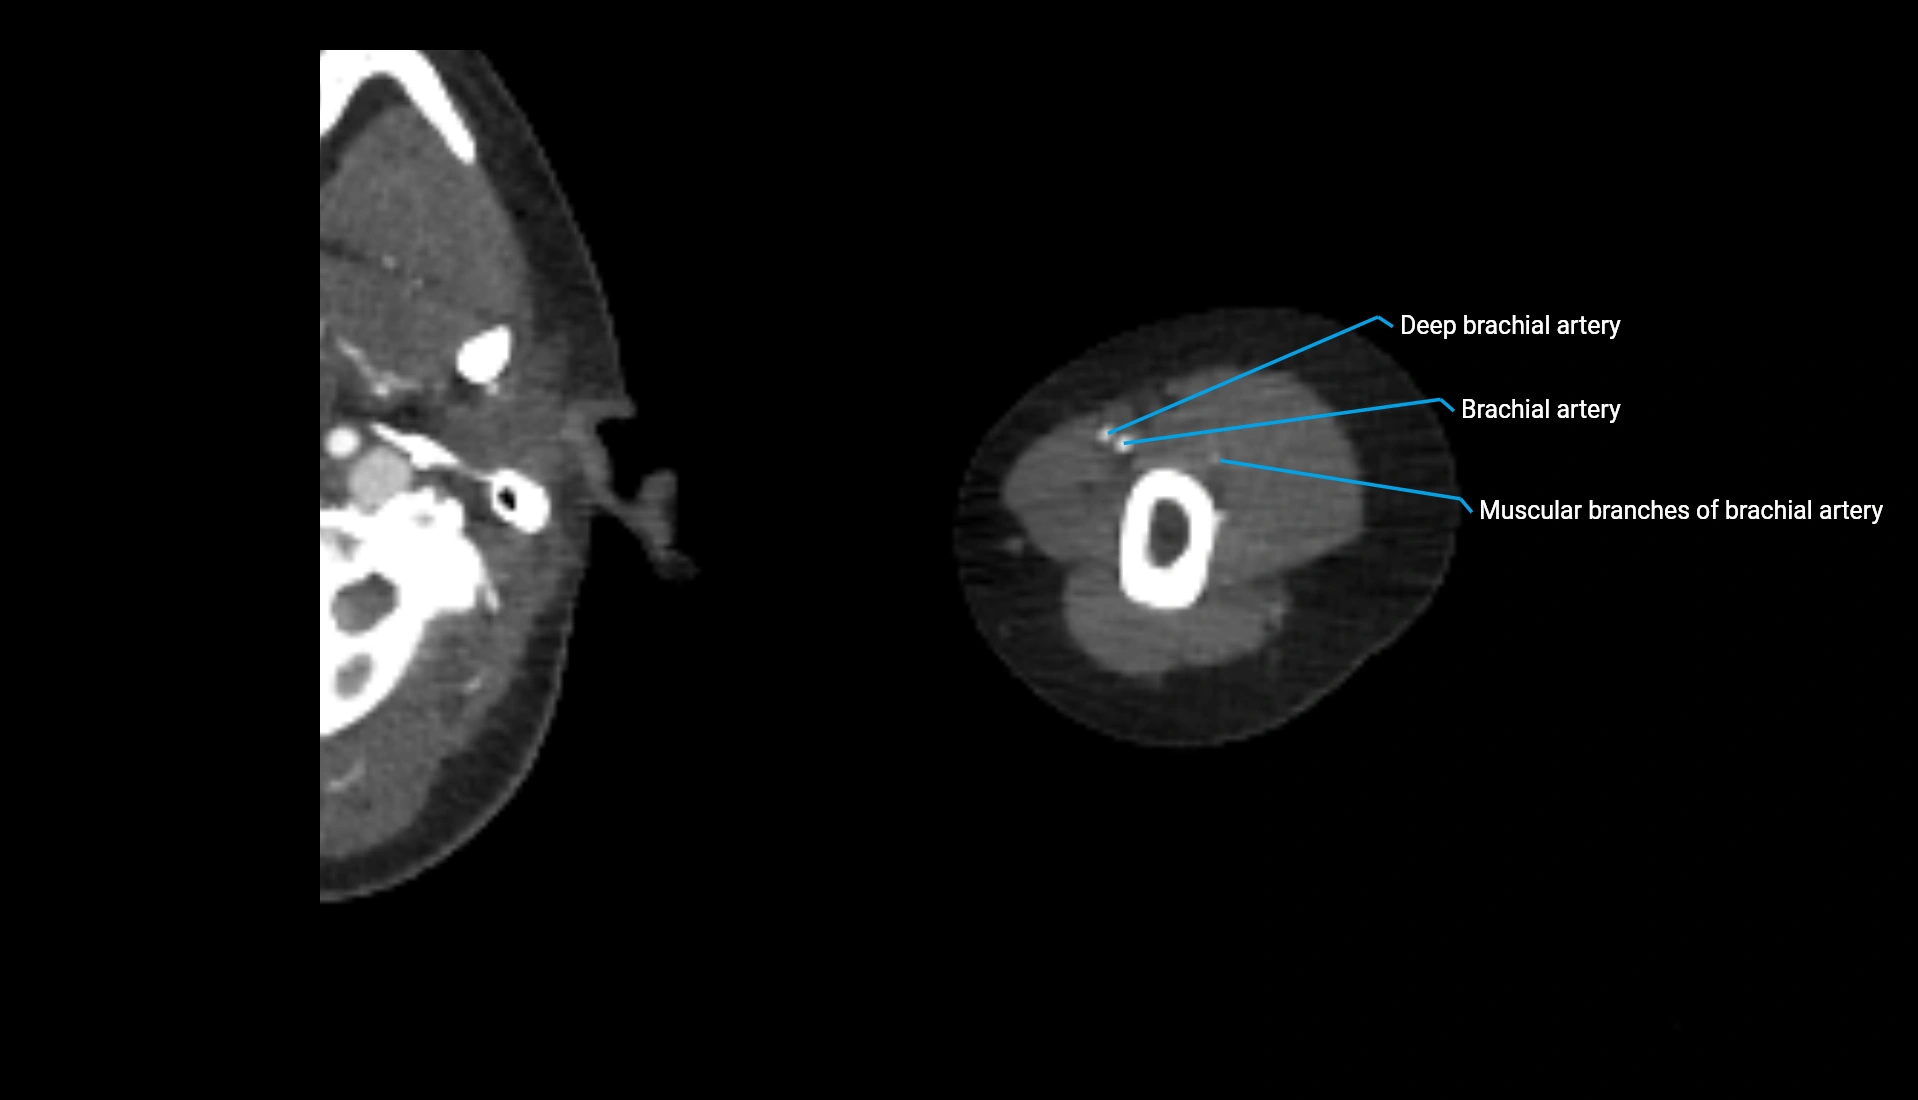

CT Appearance

Non-Contrast CT:

• Cortex: High-density, sharply defined

• Subchondral bone: Dense cancellous matrix

• Articular surface: Smooth concave contour articulating with the capitellum

• Excellent for evaluating bone integrity, alignment, and subtle fractures

Post-Contrast CT:

• Bone: No enhancement

• Joint capsule and synovium: Mild enhancement outlining the joint

• Improves contrast between soft tissues and bony margins

• Useful in detecting subtle joint abnormalities or postoperative changes